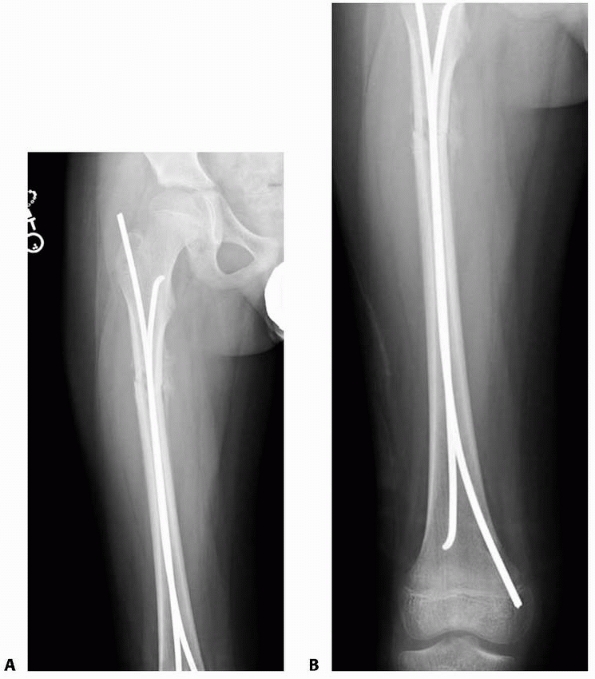

most centers throughout the world has been retrograde, with small

medial and lateral incisions just above the distal femoral physis;

however, some prefer an antegrade technique, with entry in the

subtrochanteric area. The primary advantages of a proximal insertion

site are a fewer knee symptoms postoperatively. Bourdela22

compared retrograde and antegrade (ascending and descending) flexible

intramedullary rodding in a group of 73 femoral fractures. Sixty one

fractures were treated with antegrade nails and 12 with retrograde

nails. All children with antegrade nailing had good clinical and x-ray

results; all 12 children with retrograde nails had knee pain that

impaired knee motion until the nails were removed. An antegrade

transtrochanteric approach was recommended by Carey and Galpin,32

who reported excellent results in 25 patients without growth arrest of

the upper femur and no osteonecrosis. Satisfactory alignment and

fracture healing were obtained in all patients.